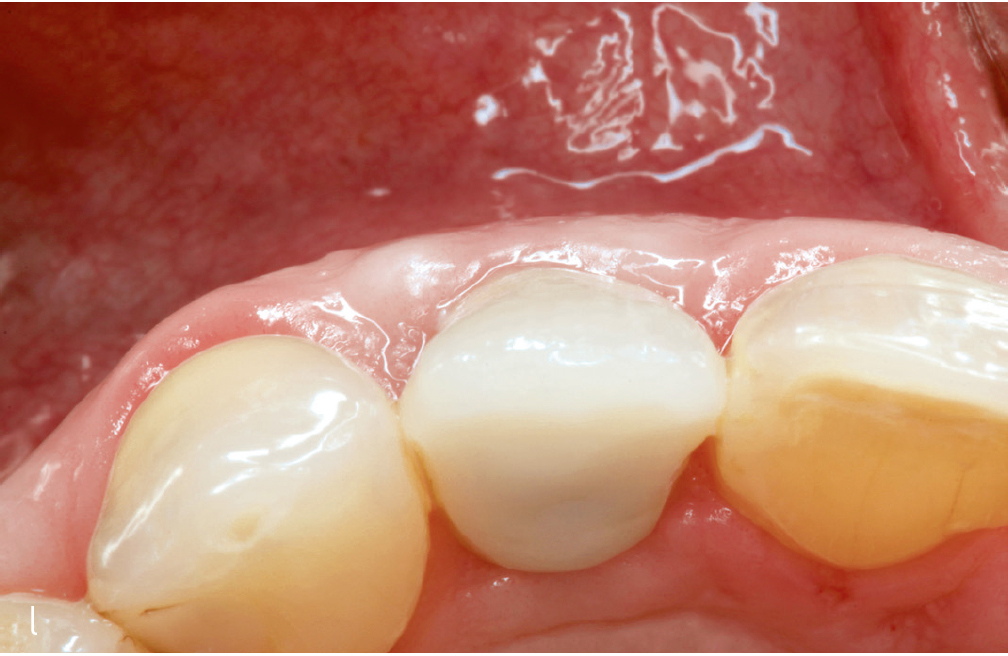

Abb. 3i bis m Falldokumentation mit Zustand nach Implantation und lateraler Augmentation alio loco: i) okklusale Ansicht mit eingebrachtem BGT vestibulär in der Region 12; j) Wundverschluss mit Naht; k) klinische Situation 9 Monate post operativ; l) okklusale Ansicht; m) klinische Parameter.